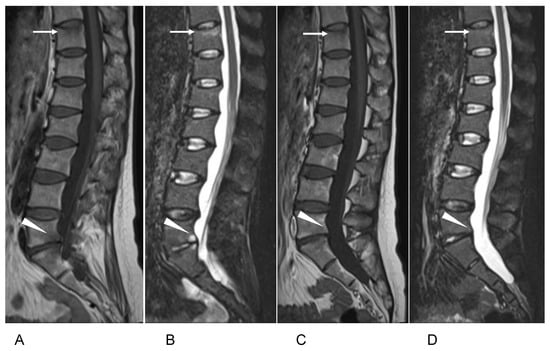

2. Case Presentation